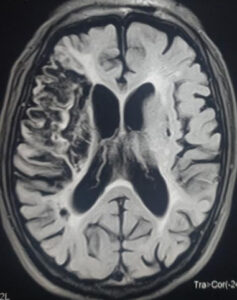

Strok atau angin ahmar merupakan masalah kesihatan yang melibatkan bahagian otak. Ia berlaku apabila salur darah tersumbat dan bekalan darah ke sebahagian otak terganggu. Sebahagian dari tisu otak akan rosak atau mati disebabkan kekurangan bekalan oksigen.

Strok jenis ini merupakan strok yang paling sering berlaku. Strok ini berlaku apabila saluran darah tersumbat, lalu menyekat pembekalan darah ke otak.

Ini menyebabkan otak tidak mendapat darah yang membawa oksigen yang mencukupi. Kemudian, mengakibatkan sel dan tisu otak rosak atau mati.

Strok jenis ini terjadi apabila terdapat pendarahan di otak. Lalu menyebabkan gangguan bekalan darah ke otak.

Pendarahan berpunca dari saluran darah di bahagian otak pecah. Ia boleh berlaku disebabkan beberapa faktor.